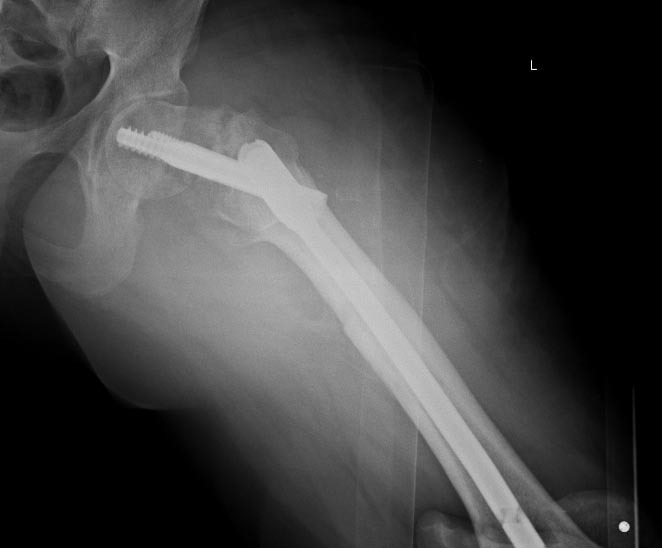

Продолжение истории, начало см. http://weborto.net/forum/1370513039/.Сегодня сделали левое бедро. Сделана аналогичная чрескожная вальгизирующая остеотомия, закрытый интрамедуллярный остеосинтез Affixus. Длинным, с учетом еще и бывшего диафизарного перелома. Были какие-то мысли насчет пластики дефекта шейки - решили воздержаться.

Александр Николаевич, любая попытка сохранить сустав у молодого пациента приветствуется. Смущает ограниченный контакт в зоне перелома, все же надо иметь ввиду несвободную костную пластику на питающей ножке в случае если через1,5-2 месяца Вы не увидите намеков на консолидацию.

Александр Николаевич, вопросы абсолютно справедливые. Предпочтение отдаются участку крыла подвздошной кости на мышечной ножке. Трансплантат располагается по передней поверхности шейки бедренной кости (во всяком случае там, где она должная быть) слегка внедряется в головку и шейку и фиксируется одним винтом в дистальном отделе в зоне б/вертела. Доступ к суставу проходит между мыщцами и достаточно мало травматичный. На эту тему в институте была защищена диссертация Карелкиным Виталием Вл-чем, в работе детально проработаны все анатомические нюансы забора трансплантата. Что касается нагрузки.... Эвакуация от себя это правильный принцип))) но ведь и позвонить могут... Если по сути, то действительно сложно оптимизировать нагрузку, но и без нее нельзя. Я бы разрешил первые 6 недель с касания пола до веса ноги. Последующая постепенная нагрузка до одного костыля к 4-м месяцам, далее - по ощущениям в зоне комфорности. Избыточная нагрузка опасна, длительная иммобилизация ничего не даст. Контрольная Р-грамма через 2-а месяца, необходимо оценить два момента - смещение имплантата и наличие признаков мозолеобразования. При отсутствии смещения и признаков регенерации целесообразна костная пластика. При наличии миграции имплантата - протезирование.... и далее по тексту. Сроки конечно могут варьировать, но не думаю что очень сильно.